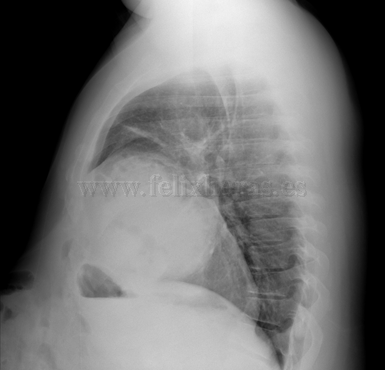

Hernia diafragmática traumática con laparocele gigante